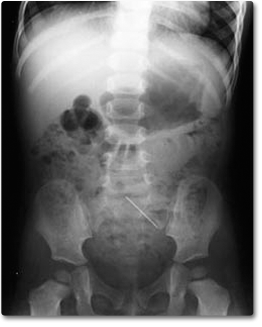

Many people pass away every year because of substandard care and facilities. The lives of many people could be saved if a disease is discovered early. Therefore, a branch called radiology is introduced in the field of medicine that uses imaging techniques to cure and diagnose disorders [1, 2, 3]. Diagnostic radiology and interventional radiology are two subcategories of radiology. Diagnostic radiology allows radiologists viewing of internal body structures. In this area, radiologists identify the underlying source of symptoms, track how effectively the body responds to treatment, and do disease screenings. The most prevalent diagnostic radiology procedures include computed tomography (CT), magnetic resonance imaging (MRI) and magnetic resonance angiography (MRA), mammography, x-ray, positron emission tomography (PET) scan, ultrasound, etc. Interventional radiologists employ imaging techniques like CT and MRI to help direct treatments. Doctors can insert catheters, wires, or other small instruments into your body with the use of imaging. Angiography, cancer treatment, needle organ biopsies, uterine artery embolization, etc are some examples of interventional radiology techniques [105]. X-rays are a form of electromagnetic radiation where the wavelength is ranging from 10 picometers to 10 nanometers, corresponding to frequencies in the range of 30 petahertz to 30 exahertz. Wavelengths of X-rays are generally longer compared to those of gamma rays but shorter compared to those of UV rays. In 1895, German scientist Wilhelm Conrad Roentgen first discovered and documented X-rays. An X-ray is a rapid, painless diagnostic that generates pictures of the internal organs and structures in your body, especially your bones. Depending on the density of the parts, the body absorbs X-ray rays when they pass through it. Dense substances like bone and metal appear white when an X-ray is observed. Muscle and fat appear as shades of gray, whereas the air in the lungs is black. In the medical field, X-rays can be used to find fractures and infections in bones or teeth, bone cancer, lung infections, breast cancer, blocked blood vessels, etc. Figure 1 shows an x-ray image.